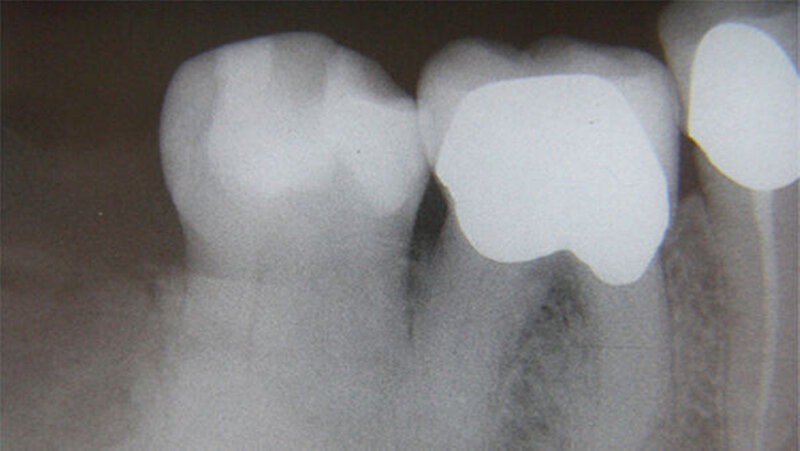

Eine 65-jährige beschwerdefreie Patientin stellte sich zur Routineuntersuchung in unserer Praxis vor. Diagnostiziert wurde eine generalisiert moderate, lokalisiert schwere chronische Parodontitis. Die im Rahmen der parodontalen Vorbehandlung durchgeführte Röntgendiagnostik zeigte eine haselnussgroße wolkige Verschattung regio 48. Anamnestisch wurde eine operative Entfernung des Weißheitszahns 48 vor ungefähr 35 Jahren angegeben.

Der Zahn 47 reagierte positiv auf den Vitalitäts-/ Sensibilitätstest. Eine dreidimensionale Bildgebung musste von der Patientin aus wirtschaftlichen Gründen abgelehnt werden. Die Verdachtsdiagnose: ein Osteom oder ein Zementom. Zur explorativen Probeexzision wurde nach minimalinvasiver Schnittführung ein Knochendeckel präpariert, was eine berührungslose Darstellung der knöchernen Veränderung erlaubte. Weil die Veränderung sehr hart und spröde war, konnte sie nicht in toto entfernt werden.